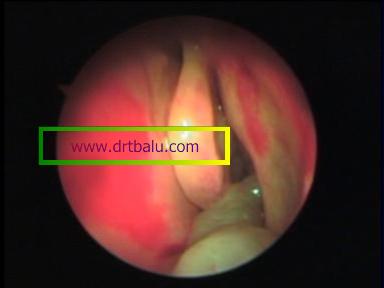

Antrochoanal polyp exiting out of accessory ostium

Anterior rhinoscopy may show the polyp as glistening polypoidal structures. They will be insensitive to touch. this feature helps to differentiate it from a hypertrophied nasal turbinate.